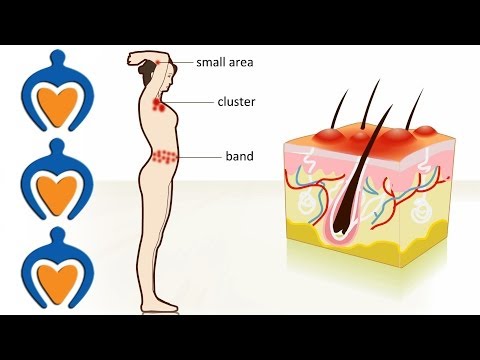

What Is Shingles / Herpes Zoster | Symptoms - Causes - Treatment

Herpes Zoster or Shingles: A Distinct Skin Rash